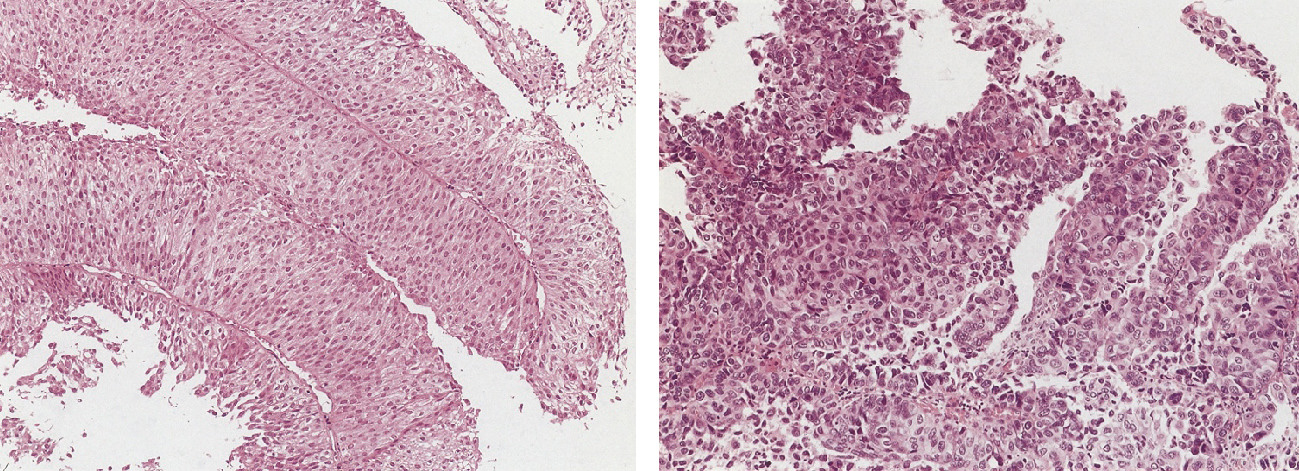

究める鏡視下膀胱全摘術・尿路変向術 Level up LRC, RARC | 三木。メジカルビュー社|泌尿器科|究める鏡視下膀胱全摘術・尿路変向。ロボット支援膀胱全摘除術(RARC) | 岩手医科大学 泌尿器科学講座。★3月精米★ 令和6年産 福井県産 いちほまれ 5kg 白米 精米。膀胱がん【泌尿器科疾患について】 - 東京慈恵会医科大学 泌尿器科。膀胱がん|KOMPAS。手術手技(膀胱全摘除術) | 領域情報 | アステラスメディカルネット。膀胱がん|KOMPAS。周術期の負担を軽減し早期社会復帰を!「ロボット支援腹腔鏡下。腎盂尿管移行部狭窄症に対するロボット支援腹腔鏡下腎盂形成術。朝倉書店『内科学』(第12版)デジタル付録。腹腔鏡下尿膜管摘出術及び左腎摘出術 - Olympus Professional。ロボット手術の定番!新品、未使用です。間違って2冊買ってしまったので、ページを開いてもいないため、本屋さんの「売上スリップ」も付いたままの全くの新品です。膀胱がんの外科治療について | 小野薬品 がん情報 一般向け。